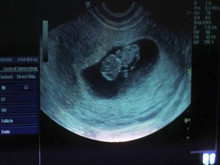

完全流产是指妊娠物全部排出,阴道出血减少,逐渐停止,腹痛消失,妇科检查宫颈关闭,...

血常规、尿液检测、B超